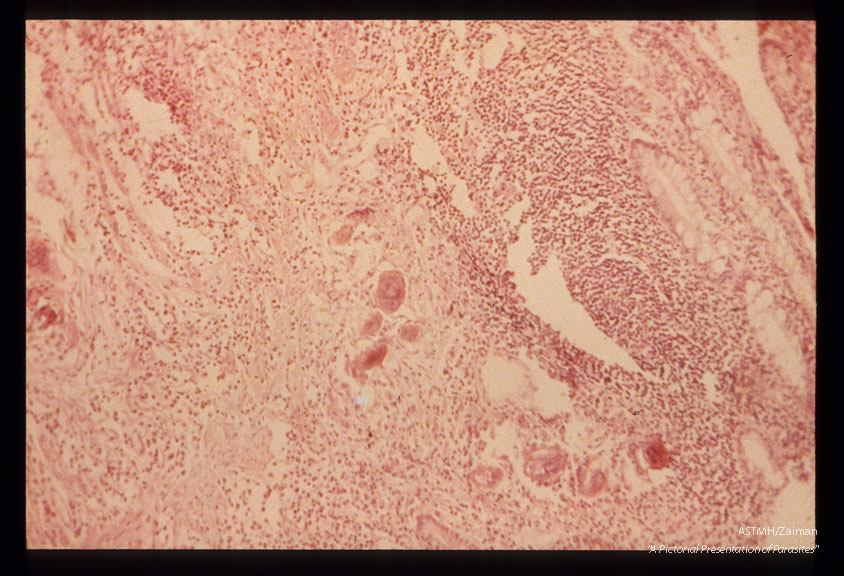

Section of rectum showing eggsand inflammatory infiltrate.

Schistosoma japonicum

Description: Section of rectum showing eggsand inflammatory infiltrate.